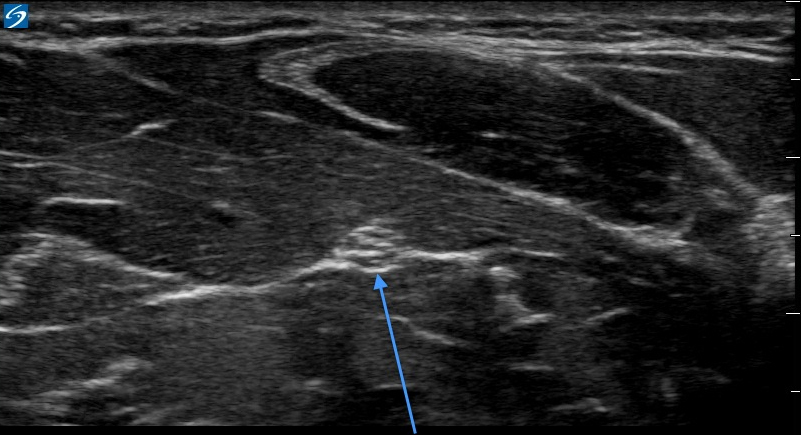

Antebrazo X-Porte: Imagen de eje transversal del nervio mediano

Flecha azul: Antebrazo - Eje trasversal del nervio mediano